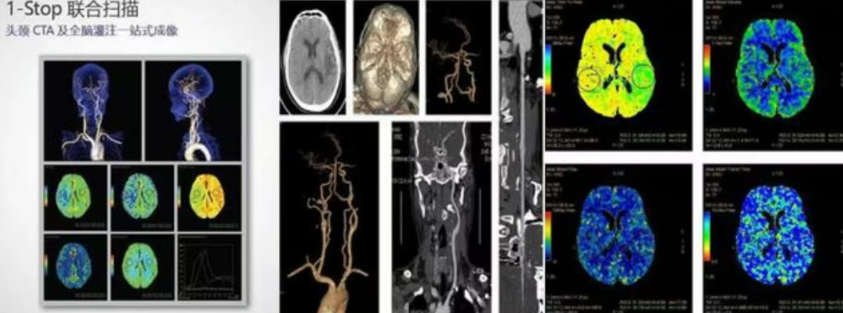

脑卒中诊疗:一键式高效成像

面对脑卒中这一“时间就是大脑”的疾病,GE Revolution 256排CT 实现无限制1 - stop脑卒中超快速一站式成像。一次造影剂注射、一次扫描,即可同步完成头颅平扫、头颈CTA、颅脑多期增强和全脑灌注成像。

发病6小时内,5分钟方案快速评估颈动脉狭窄与侧支循环;发病6 至 24小时,10分钟方案整合多维度信息。助力医生更快鉴别出血性与缺血性卒中,加速救治流程,为患者抢回宝贵生机。